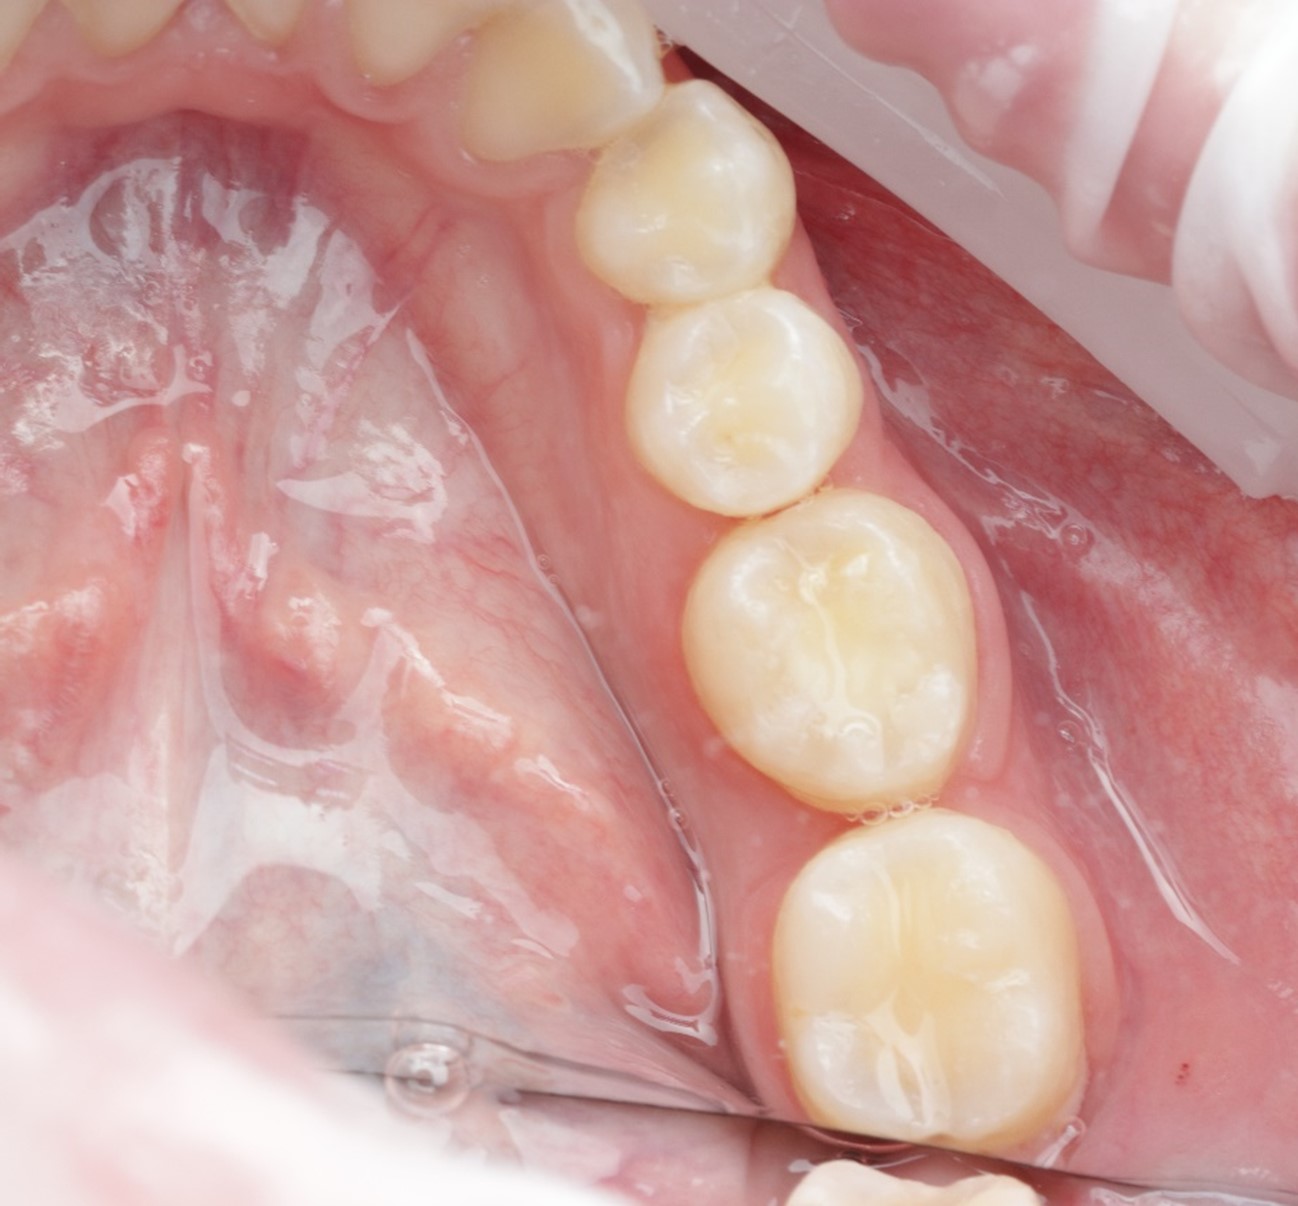

Métodos: Se llevó a cabo un caso clínico en una paciente de 40 años con fracaso de restauración fija dentosoportada en el incisivo central superior izquierdo, asociado a caries radicular subgingival con mal pronóstico restaurador. Tras la evaluación clínica y radiográfica, se indicó la exodoncia atraumática del diente afectado. Inmediatamente después, se realizó la colocación de un implante postextracción. El defecto periimplantario (gap) fue rellenado con un xenoinjerto óseo bovino. De forma simultánea, se llevó a cabo un injerto de tejido conectivo con el objetivo de optimizar el volumen y la estabilidad de los tejidos blandos periimplantarios. Se procedió a la colocación de una restauración provisional inmediata atornillada, diseñada para preservar el perfil de emergencia y guiar la cicatrización de los tejidos periimplantarios. Tras un periodo de cicatrización de cuatro meses, se colocó la restauración definitiva atornillada.

Resultados: El seguimiento clínico y radiológico evidenció una correcta osteointegración, estabilidad de los tejidos periimplantarios y un resultado estético satisfactorio, mantenido a los cuatro años.